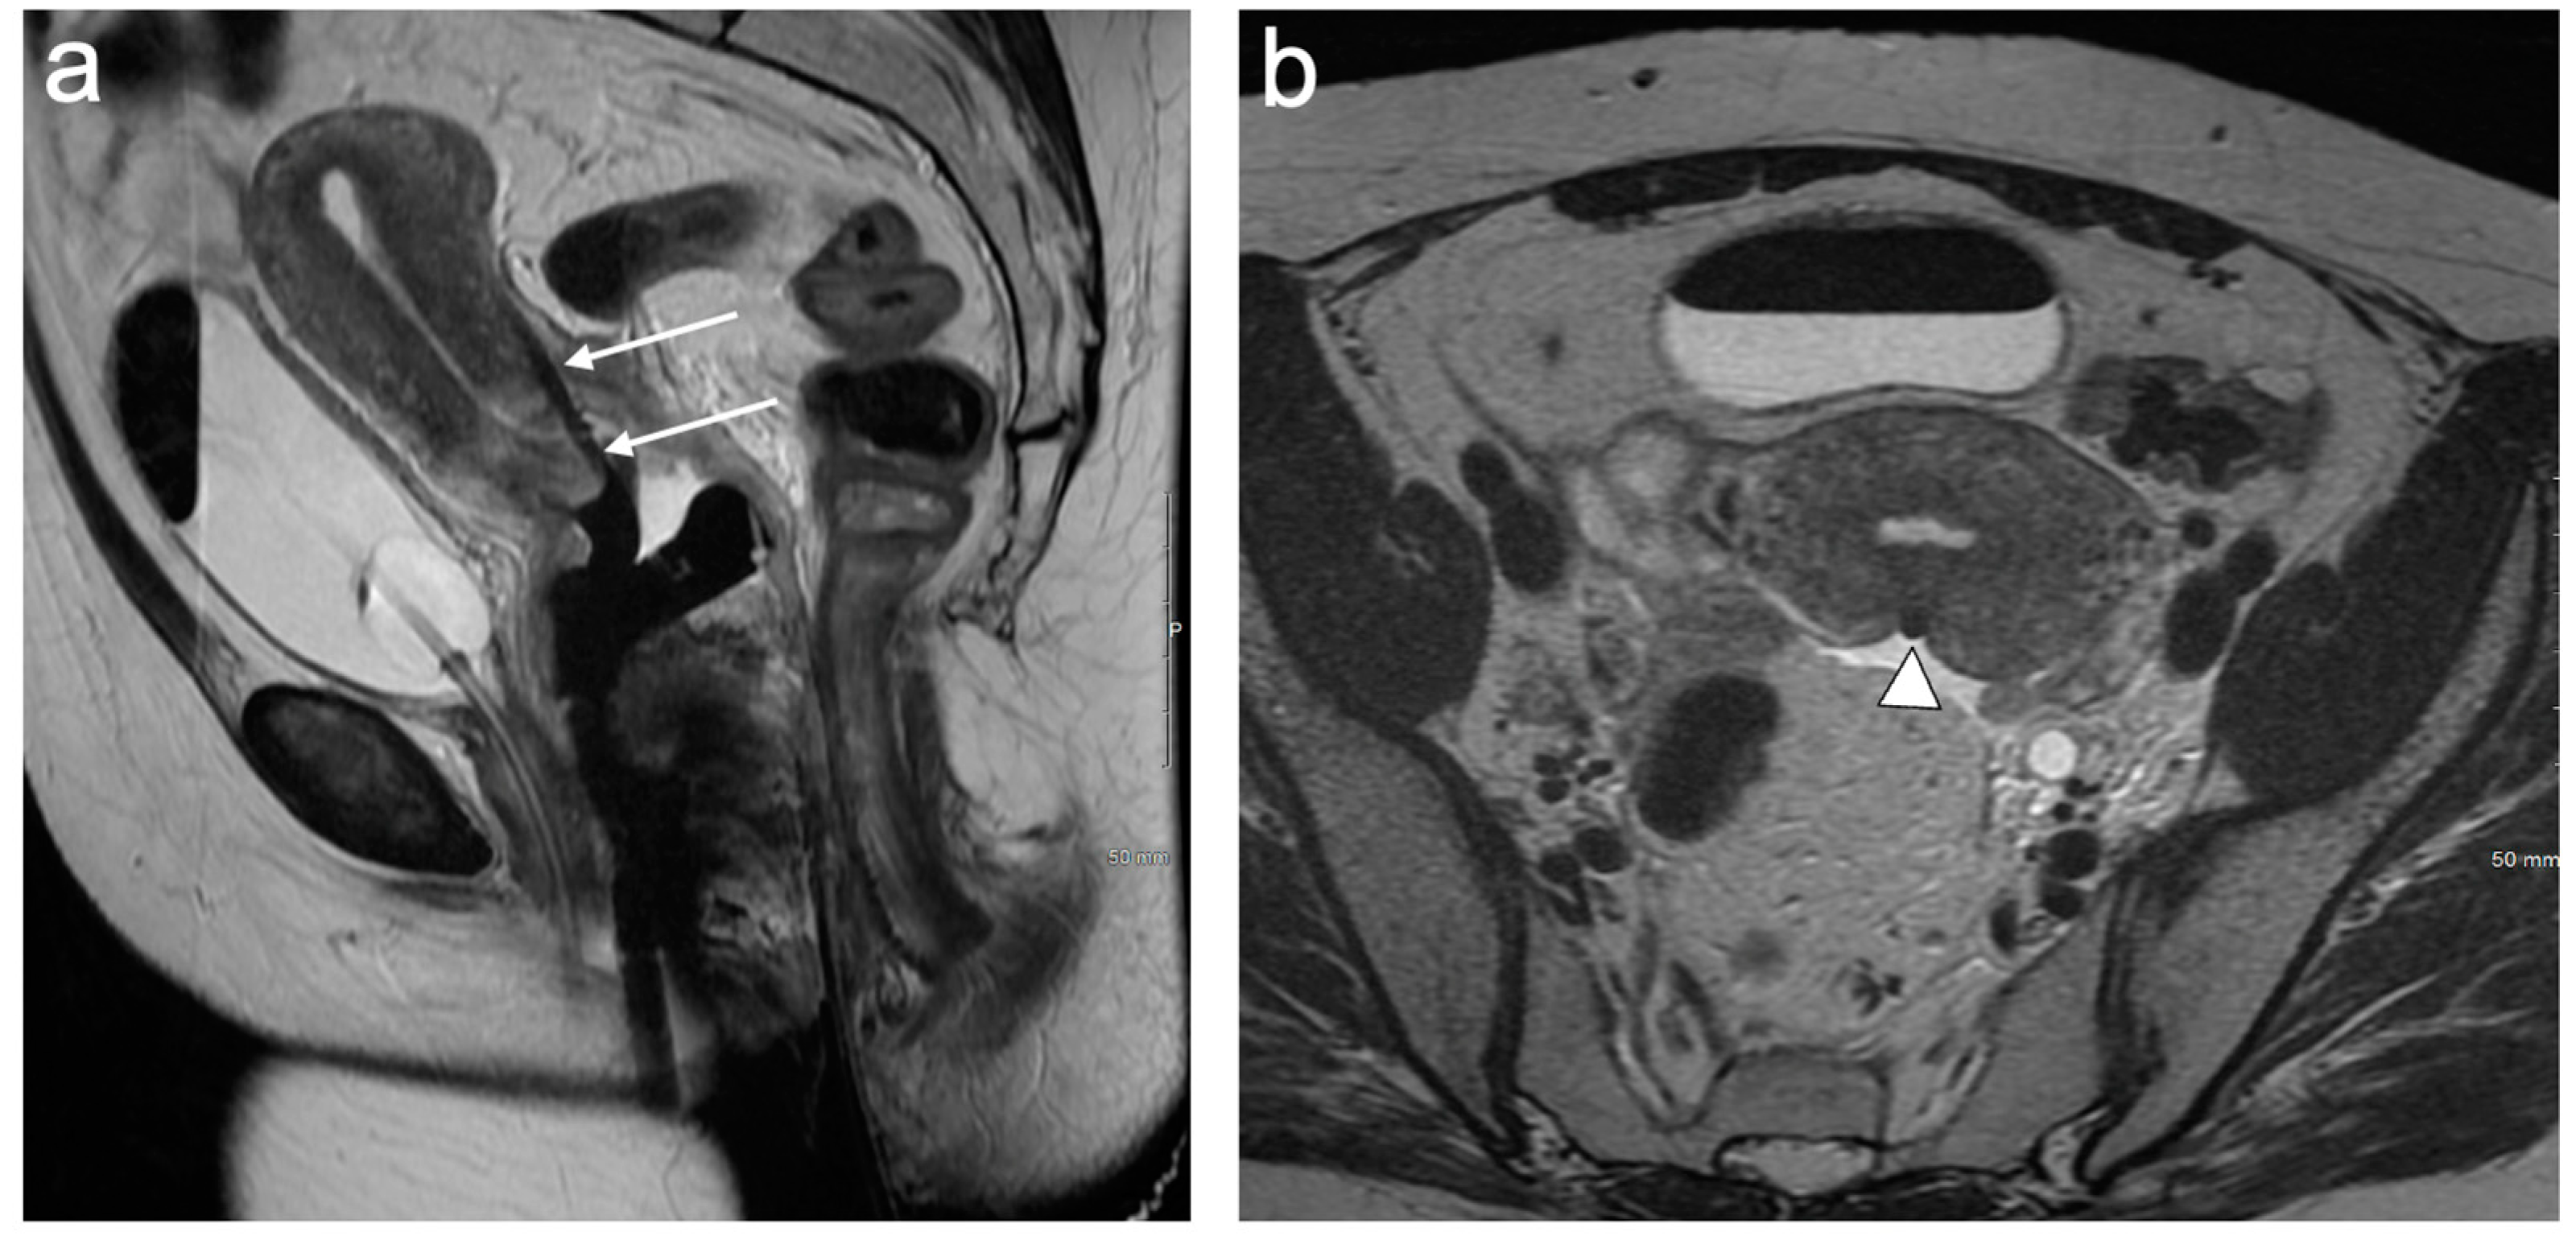

4. FIGO Stage I

5. FIGO Stage II

6. FIGO Stage III